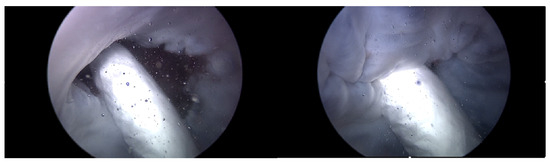

3.2. Second Scenario—Heart 2 without the Pivot-TR

Heart 2 in Figure 11, like Heart 1, represents a porcine heart exhibiting standard cardiac functions. It was employed to verify whether the heart simulator could consistently reproduce results comparable to those observed with Heart 1. Furthermore, experiments were planned with Pivot-TR installed. Figure 12 reveals results that closely resemble those of Figure 8. However, a distinct variation was observed with Heart 2. Unlike Heart 1, the TV displayed alternating patterns of normal and abnormal functionalities—a phenomenon subsequently termed the “Mixed phase”. A notable observation was that when the flow rate of the Harmonic Vibration Pump increased from 60 to 70 cc/min, only abnormal TV activity was evident.

Figure 11. Endoscopic image of Heart 2 (valve open, normal valve closed, abnormal valve closed).

Figure 15. Endoscopic image of Heart 2 with Pivot-TR (valve open, normal valve closed).